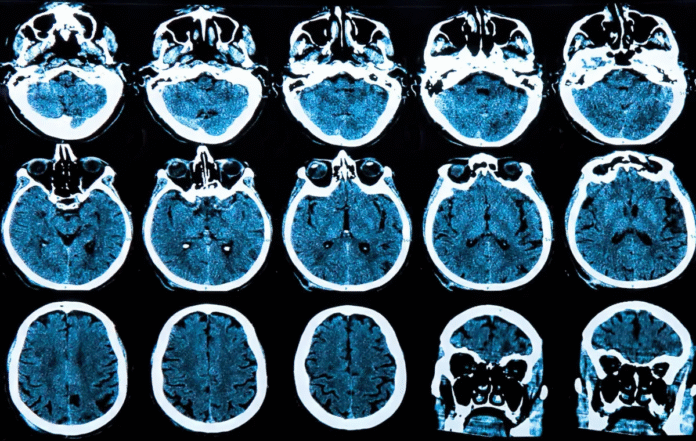

Esta é a primeira vez que um estudo mostra desaceleração significativa na progressão da doença de Huntington. A terapia genética é realizada através de uma cirurgia de grande porte no cérebro dos indivíduos afetados e, se aprovada, deve custar caro.

A condição é causada por uma única mutação genética no gene HTT, responsável por produzir a proteína huntingtina. Nos portadores da mutação, é produzida a huntingtina mutante, que causa danos crescentes no cérebro ao longo dos anos.